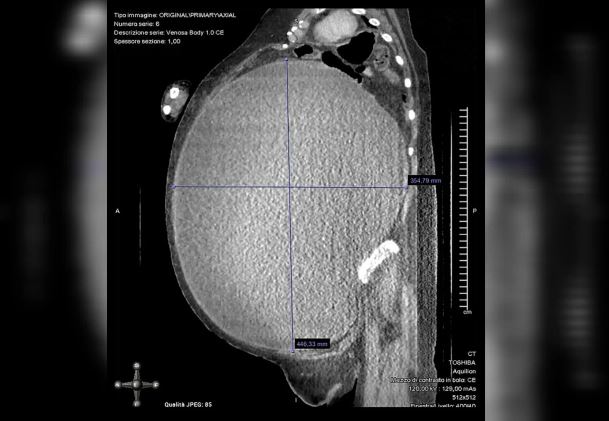

Ela precisou então fazer um exame de sangue, onde foram identificadas várias proteínas circulando em seu corpo que sugeriam a presença de um tumor, o que a levou a fazer um ultrassom, que comprovou o tumor de 5 quilos e 40 centímetros de diâmetro.

Uma equipe com especialistas de várias áreas decidiu fazer a cirurgia, onde os médicos drenaram cerca de 37 litros de um fluido amarronzado que havia se acumulado na barriga da paciente.

O peso acumulado pelo cisto e o fluido sugeria que ela tinha um grau 3 de obesidade. Quando entrou no centro cirúrgico para fazer a retirada do cisto, ela estava com 123 quilos. Após a operação, o peso dela baixou para 70 quilos.